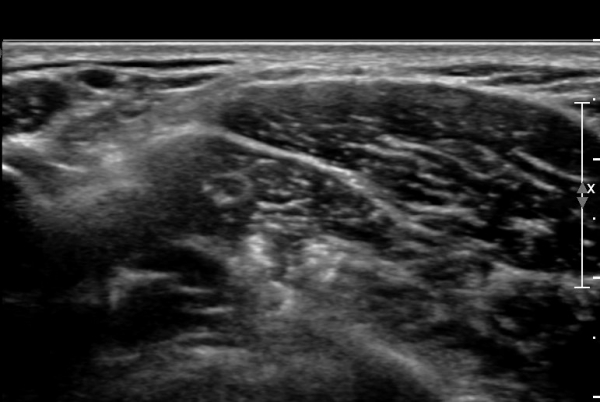

ÃÊÀ½ÆÄ ¼Ò°ß : ¸ñ ¿ÜÃø Á߾ӺΠȾ´Ü¸é°Ë»ç»ó Èä¼âÀ¯µ¹±Ù ÈÄ¹Ý °ß°©°Å±Ù Ç¥Ãþ¿¡¼­ ôÃߺνŰæÀÌ Àú¿¡ÄÚ

¿øÇü ±¸Á¶¹°·Î °üÂûµÈ´Ù(»çÁø 1, 2, 3).